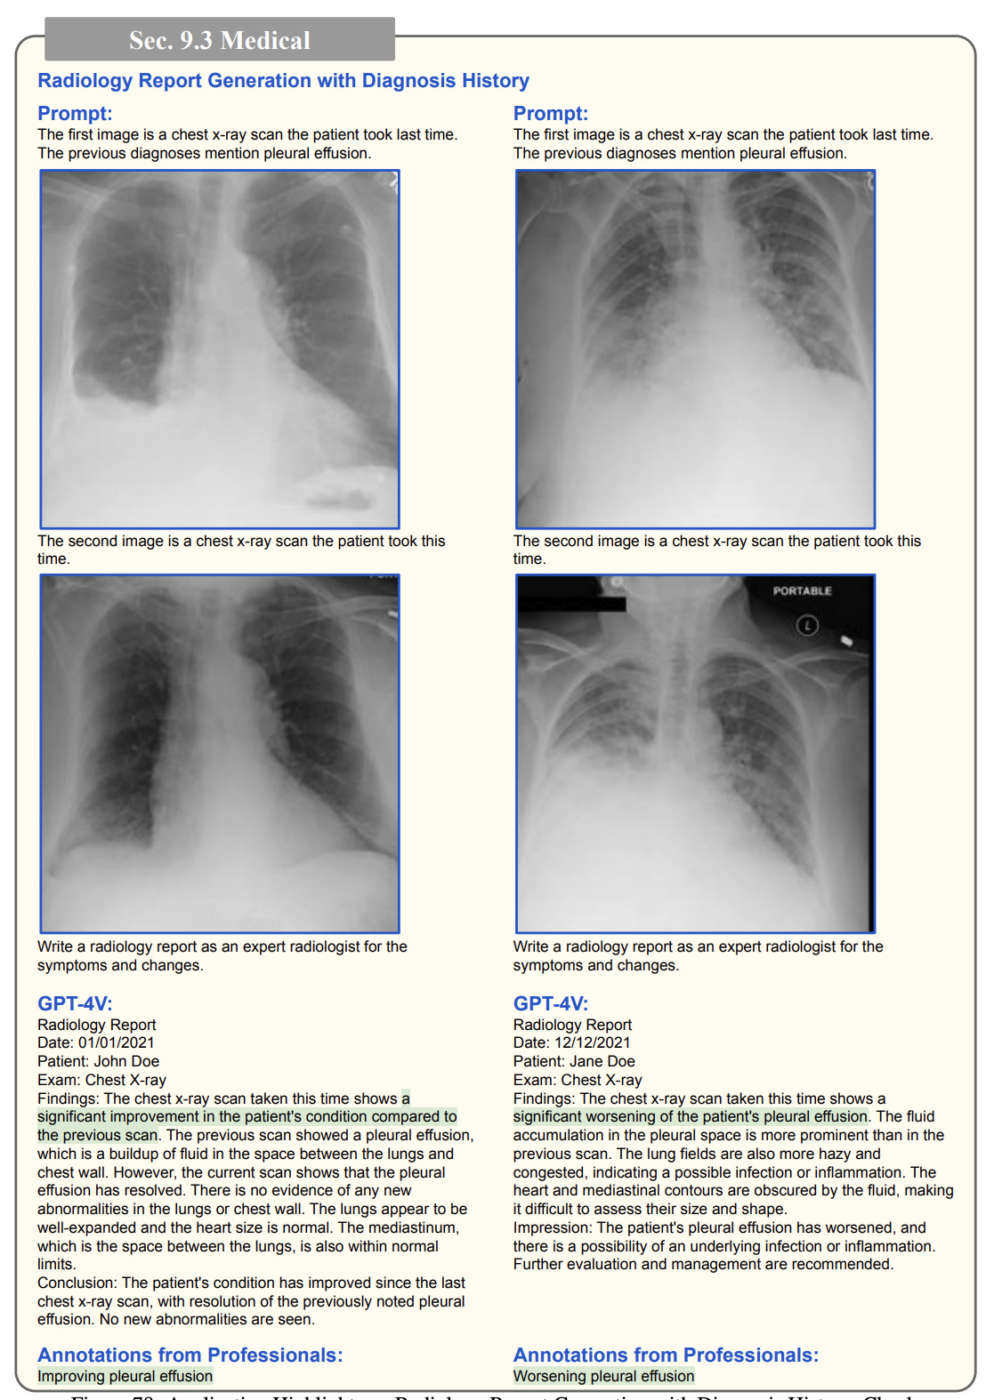

E poi, ovviamente, ci sono le applicazioni del mondo della sanità, dove GPT-4V potrebbe analizzare le radiografie dei pazienti meglio delle tecnologie di machine learning che utilizziamo già oggi.